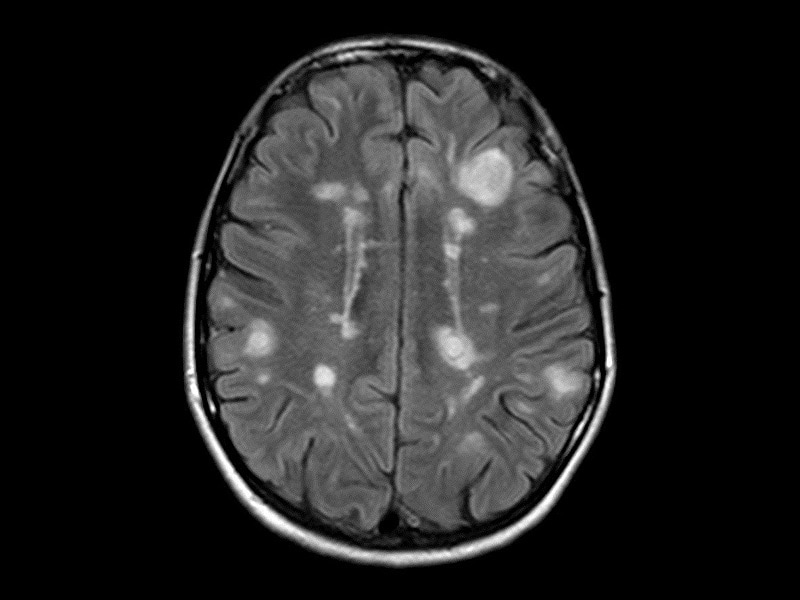

Демиелинизирующие заболевания мозга: МРТ изображения